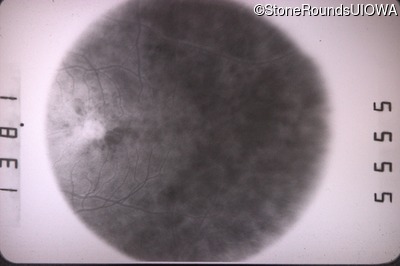

Optical Coherence Tomography - Right - 20/50 -3

Exemplar / OCT Stack